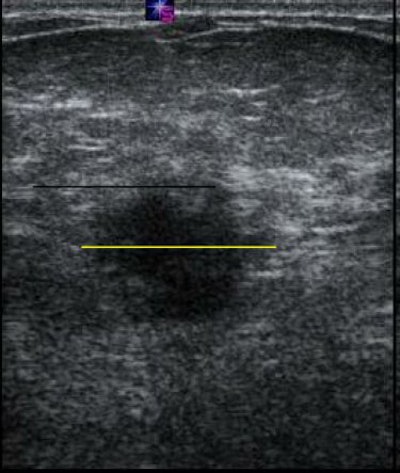

| Biopsy-proven IDC. Above, a conventional ultrasound image. Below, EI acquired at the same time with the same signals. The lesion in the elasticity image is much larger than the image in the conventional ultrasound, which is more likely to correspond to a malignant lesion. Images courtesy of RSNA. |

The lesions evaluated included infiltrating ductal carcinoma (IDC), ductal carcinoma in situ (DCIS), fibroadenomas, and cystic lesions. The average lesion size was 10 mm. Side-by-side, simultaneous sonographic images of the breast were produced in B-mode and with EI. The radiologist at each site measured the lesions and classified them as benign or malignant. Biopsy and its pathological results served as the reference standard.

In addition to differences in shading compared to normal tissue, EI depicted lesion stiffness or hardness, as well as changes in size. "Malignant lesions appear to be larger on the elastogram, while benign lesions appear to be smaller," Barr stated.